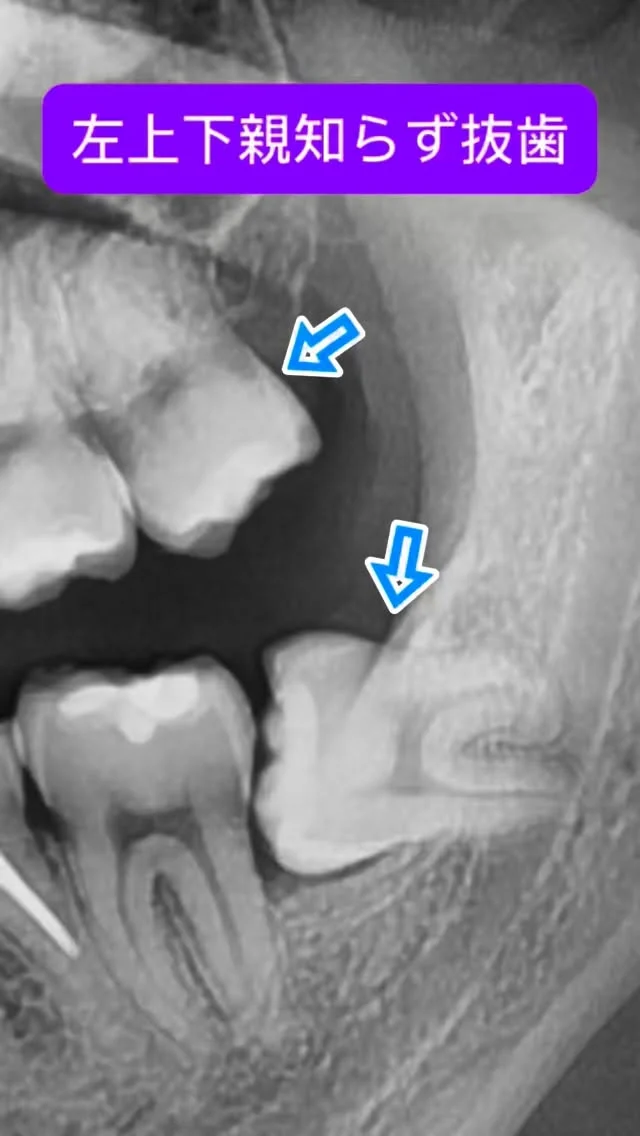

大学病院や総合病院で長年、親知らず抜歯や歯根端切除術などの小手術から、全身麻酔下で行う顎矯正手術(骨切り)、口腔腫瘍、インプラント治療など幅広い口腔外科診療・手術に携わってきました。

これまでに数多くの難症例を担当し、「安全、スピーディーかつ合併症を低減する手術」を常に意識してきました。特に骨切り手術では、機能面の改善だけでなく、顔貌のバランスや審美性にも配慮し、口元の自然な美しさを追求しています。

親知らずや顎の形のお悩み、外科的な処置に不安をお持ちのかたも、ぜひ一度ご相談ください。専門医として、丁寧に寄り添いながら適切な治療をご提案いたします。